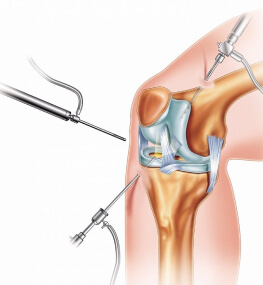

- Артроскопія суглоба;

- Ендопротезування суглобів.

Заміна суглоба - операція не з простих, але сьогодні її роблять настільки часто, що для кваліфікованого лікаря в її проведенні немає нічого складного.

Ендопротезування кульшового суглоба (ціна є в прайсі) відновлює повністю функції нижніх кінцівок і дозволяє людині вільно, без дискомфорту пересуватися. Адже пошкодження тазостегнового суглоба призводить до того, що людина повністю перестає пересуватися через сильний біль.

Крім операції під назвою - ендопротезування кульшового суглоба, ціна на яку цілком доступна у нас, досить-таки часто в госпіталі проводиться і заміна колінного суглоба (ціна залежить від типу операції). Заміна суглоба в коліні - одна з найбільш затребуваних операцій.

Ендопротезування колінного суглоба в залежності від того який ступінь пошкодження тканин, може бути тотальною або частковою.

Операція по заміні суглоба є абсолютно безпечною. При цій процедурі використовується високоякісний протез, який підбирається індивідуально під кожного пацієнта.

Операція, яка позбавляє від постійного болю - заміна суглоба (ціна залежить від місця локалізації та типу операції) поверне людину до колишнього життя, адже виконується за допомогою нових технологій, що гарантують швидке одужання.